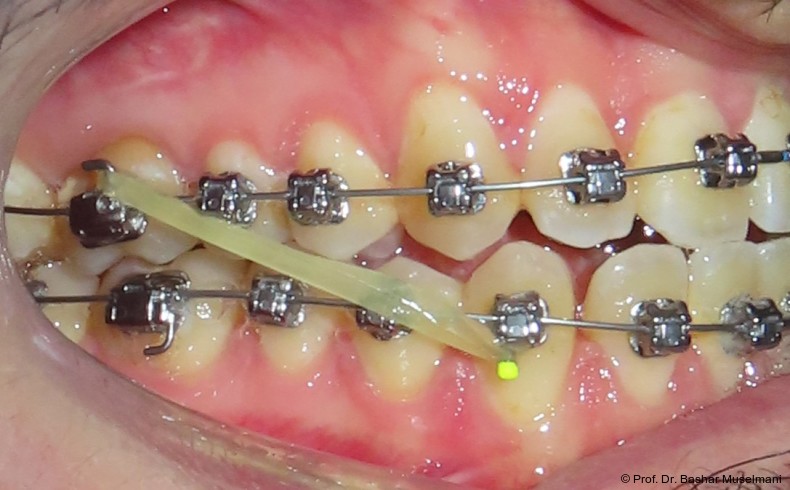

Die Abbildungen 1 bis 3 zeigen die initiale klinische und radiologische Ausgangssituation.

Zur sagittalen Korrektur wurden intermaxilläre Klasse III-Gummizüge eingesetzt.

Zu Beginn der Nivellierungsphase wurden in beiden Kiefern 0.013" CuNiTi-Bögen eingesetzt (Abb. 4a–e).